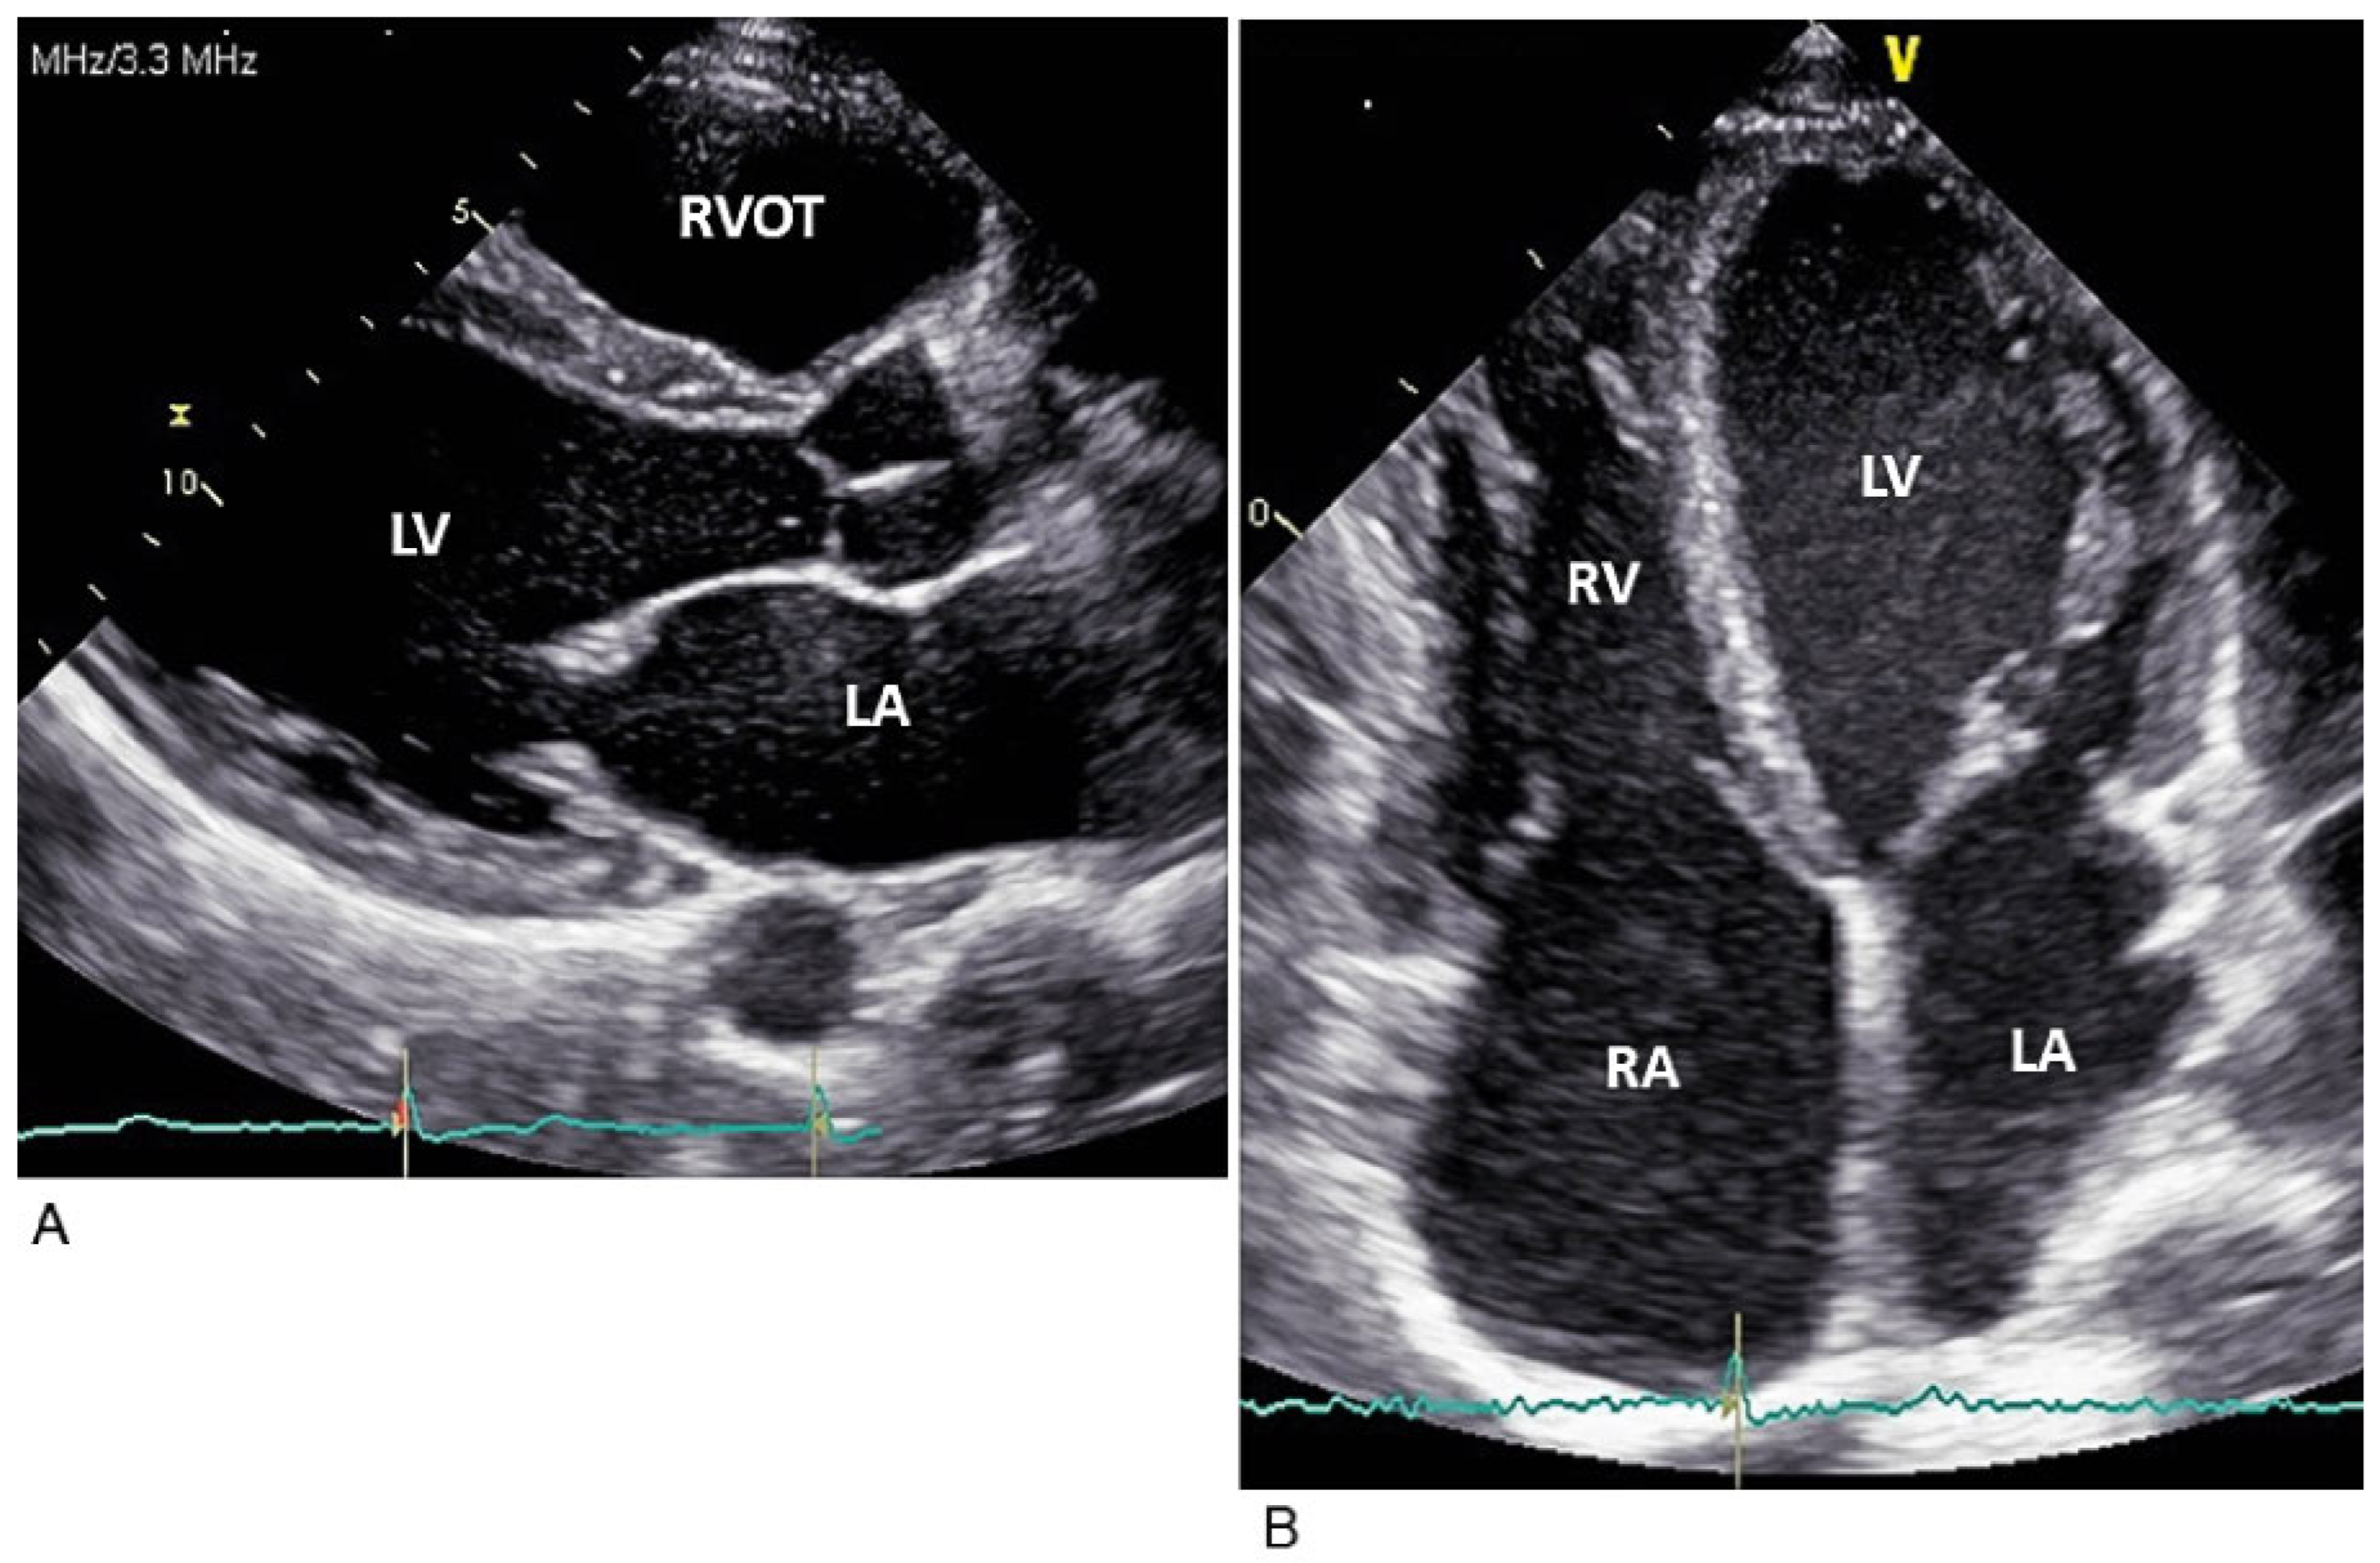

Case report

A 37-year-old male patient was referred to our cardiology division with a longstanding and worsening history of short episodes of dizziness and reduced effort tolerance. He denied any syncope, palpitations or chest pain. His medical history was unremarkable and he took no medication. Family history was negative for cardiac diseases at a young age or premature sudden death. On clinical examination, the patient appeared in good general condition. He was bradycardic at 40 bpm and normotensive; heart and lung auscultation was normal, the jugular veins distended. The resting ECG displayed a junctional rhythm at 35 bpm with complete right bundle-branch block and no atrial electrical activity (Figure 1). A chest X-ray showed cardiomegaly without pulmonary congestion. During a 24-hour Holter ECG, no atrial activity was discernible and a constant bradycardic junctional rhythm was noted, with a mean heart rate of 36 bpm. Moreover, 83 episodes of asystole lasting more than 3 seconds were recorded, of which 11 lasted more than 6 seconds, with the longest episode in the night being of 10.5 seconds duration (Figure 2). There were no serious ventricular arrhythmias and only 62 isolated premature ventricular beats were registered. An exercise stress test confirmed the reduced effort tolerance and absent atrial electrical activity, and revealed a severe chronotropic incompetence with maximum junctional heart rate of 88 bpm (Figure 3). The echocardiogram showed a moderate dilatation of all cardiac chambers (Figure 4) with normal biventricular systolic function, absent mechanical activity of both atria, and systemic congestion (as shown in Figure 5 for the left atrium). Brain natriuretic peptide was moderately elevated (563 ng/l, reference range <100 ng/l), as were cholestatic enzymes (gammaglutamyltransferase [GGT] 210 U/l, reference range <71 U/l). Cardiac magnetic resonance imaging confirmed the moderate dilatation of the heart chambers with normal biventricular systolic function and did not reveal ventricular myocardial fibrosis or evident atrial parietal thickening or fibrosis. An intracavitary thrombus, particularly in the left atrial appendage, was also excluded. An electrophysiological study and genetic analysis were refused by the patient. Nevertheless, all clinical and paraclinical findings were consistent with a total atrial standstill, possibly idiopathic. Because of the severe symptomatic bradycardia, a pacemaker was implanted. During the procedure, no electrical activity was recorded in the whole right atrium and no atrial capture was obtained even at maximal output (10 volts, 1.5 msec.). Therefore, a single-chamber ventricular pacemaker was implanted. Oral anticoagulation therapy was considered, but we decided against it in the face of a CHA2DS2-VASc score of 0 and the absence of left atrial appendage thrombus.

Atrial standstill, first described by Chavez et al. in 1946 [1], is characterised by the absence of electrical and mechanical activity of the atria. The ECG usually displays no discernible P waves and a regular bradycardic junctional rhythm [2,3]. Effort-related chronotropic incompetence and transient asystole are common, as in our patient [4,5]. The atrial mechanical dysfunction can be readily detected on an echocardiogram by the absence of an A-wave in transmitral or transtricuspid flow, by the lack of telediastolic opening of the mitral (or tricuspid) valve, as our case nicely showed, and by the absence of active atrial contraction in tissue Doppler imaging [2,3]. Atrial standstill is a rare but serious condition, since the longstanding profound bradycardia and the loss of atrial function can have severe haemodynamic consequences, potentially leading to syncope, heart failure and, very rarely, sudden cardiac death. Cardiac arrest can be caused by extreme bradycardia or pause-related malignant ventricular arrhythmias, particularly when atrial standstill is associated with an underlying cardiopathy [6,7,8,9]. Moreover, the dysfunctional and dilated atria with consequent blood stasis can cause thromboembolic events, as in atrial fibrillation [5,6]. Our patient complained of dizziness, effort intolerance and systemic congestion.

Figure 5. Transmitral pulse Doppler imaging (A) showing the absence of A waves and parasternal M-mode at the level of the mitral valve (B) showing the absence of the telediastolic opening of the mitral valve, demonstrating the absence of the mechanical activity of the left atrium. M-mode imaging of the inferior vena cava (C) showing systemic congestion. E = E-wave; IVC = inferior vena cava.